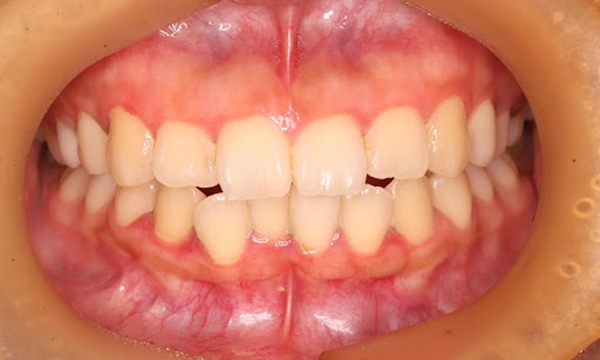

健康な歯ぐきの特徴

健康な歯ぐきは、綺麗なサーモンピンク色で、歯と歯の間が三角形でうまっています。近くで見ると、表面にみかんの皮のような細かなつぶつぶがあります。痛くない程度の力で歯ブラシの毛先を歯ぐきに当てて磨いてみましょう。出血が起こらなければ、健康な状態だといえます。

健康な状態の歯ぐきの写真